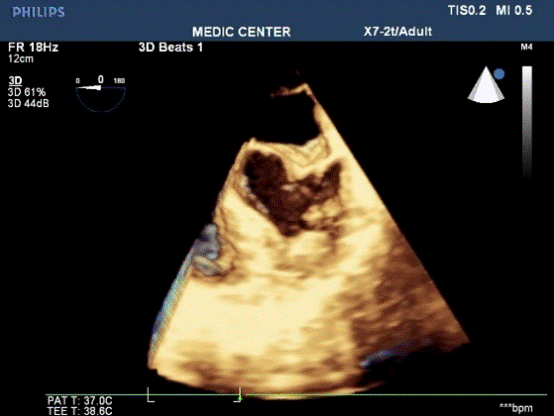

TEE visualized better the membrane and its anatomical relation on the most views as 0°, 45°, 60°, 90° and 135°.The thin membrane lied above the left atrial appendage on the 60° TEE image, the accessory atrial chamber received all pulmonary veins. Especially the 135° view demonstrated very clearly the site and size the of membranous opening, the fenestration located next to the ascending aorta and the anterior mitral leaflet and large with 11 mm in diameter. The images were obtained from 3D TEE also visualized the separated membrane with large opening (Figures 3-12).

Figure 12. Live 3D TEE of the related patient with the dividing membrane

Transesophageal echocardiographic 450, 600 and 900 views define the relationship between the membrane and the LAA, then allow differentition from supramitral ring. The 600 view of this patient demonstrated LAA locating inferior to the membrane, this anatomical finding confirmed the diagnosis of cor triatriatum. Transesophageal echocardiogrphy can be useful to detect associated lesions as ASD, VSD, anormalous pulmonary veinous return. Combined 2D TTE and 2D TEE are often the initial imaging modalities of choice when assessing anatomy and physiology in this congenital defect, adjunctive 3D TEE may improve the diagnosis of cor triatriatum and visualization of the culprit membrane in the way not possible by standard 2D imaging15.

Transesophageal  echocardiography 1350 view in this case was the best one to visualize the undulating  membrane that attached to the LA wall and leaved a large opening with non-accelerated laminal flow. 3D TEE is a more recent diagnostic tool providing additional information, able to demonstrate the entire membrane, the size, the location and the number of openings in the dividing membrane. Righab Hamdan et al. reported the crescent shape of the membrane view from the pulmonary veins on 3D TEE in a patient with obstructive cor triatriatum sinister associated with atrial flutter and secundum atrial septal defect.